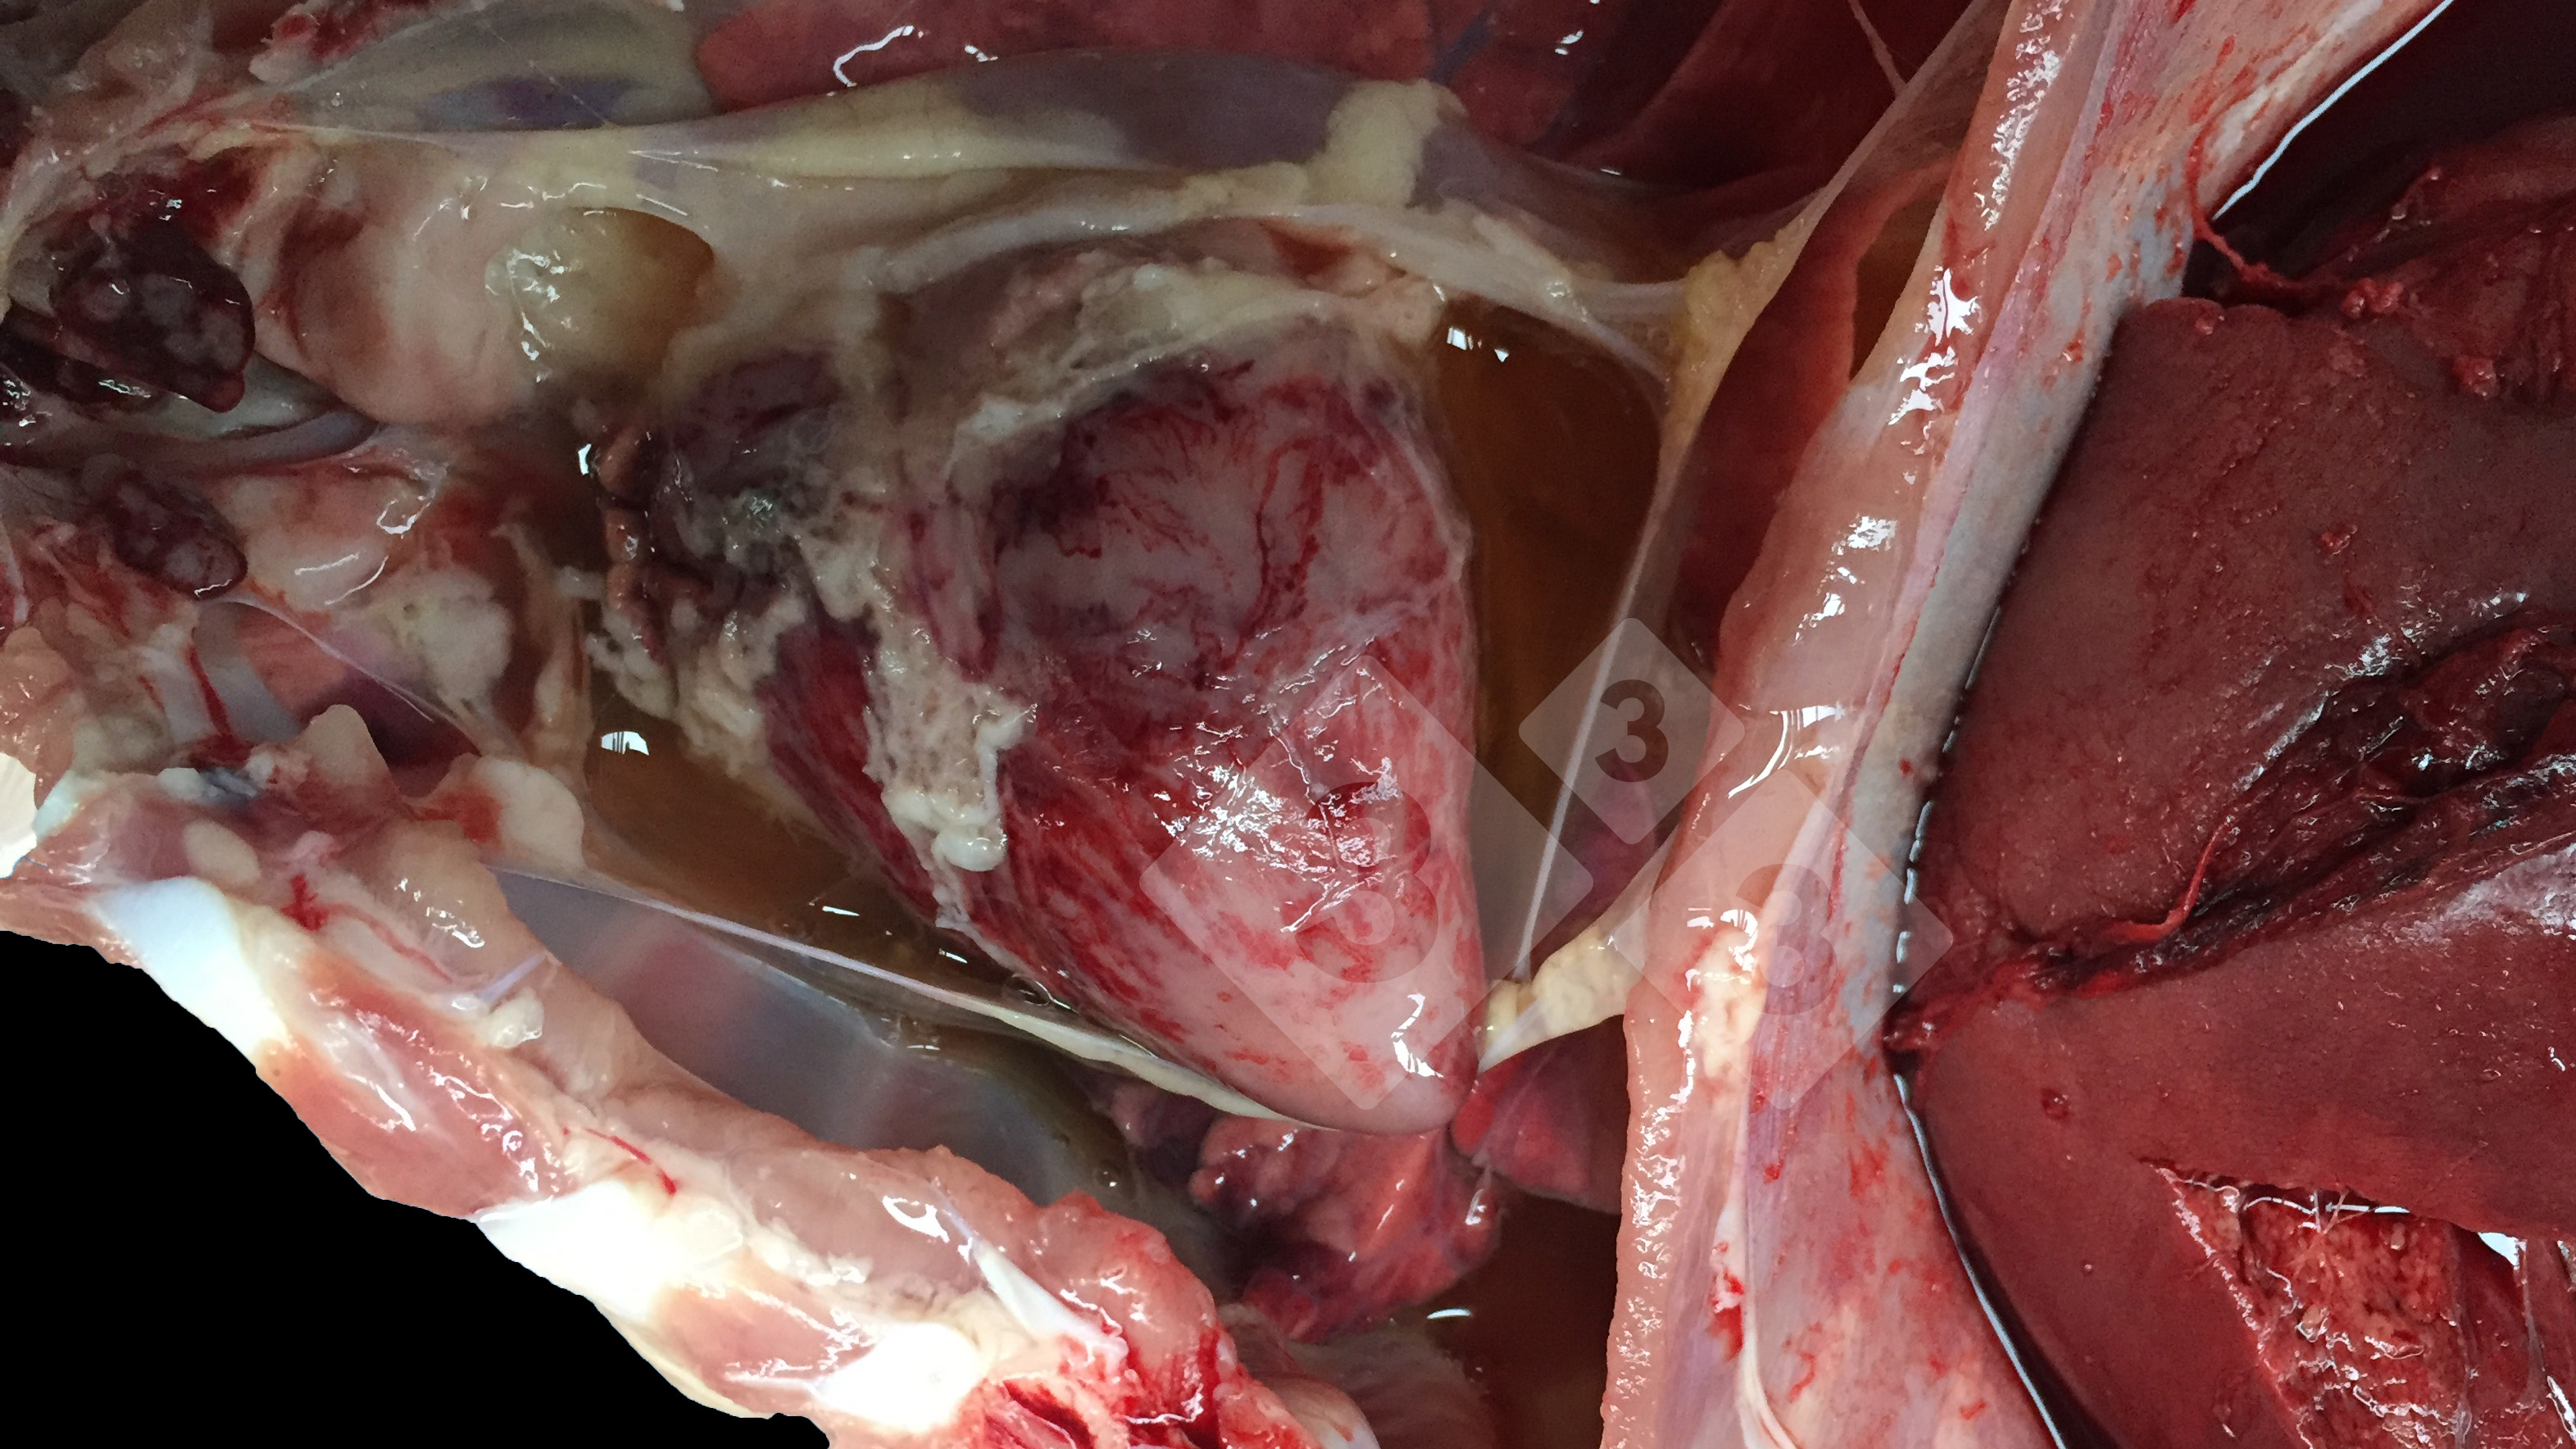

Przypadek to choroba morwowego serca morwowego u 8-tygodniowych świń, gdzie dochodziło do nagłej śmierci zwierząt.

Poziom witaminy E w diecie tych świń wynosił 50 mg / kg zamiast zalecanych 250 mg / kg po odsadzeniu i 150 mg / kg cztery tygodnie później. Witamina E jest niezbędna do optymalnego funkcjonowania i metabolizmu układu mięśniowego, nerwowego, krążeniowego i odpornościowego świni. Główne kliniczne objawy tego złożonego niedoboru wydają się wynikać z wpływu na metabolizm energetyczny. Najciężej dotknięte komórki świni to hepatocyty i komórki mięśniowe w sercu i mięśniach szkieletowych. Zespół rozwija się w wyniku zastoinowej niewydolności serca połączonej z hydropericardium.